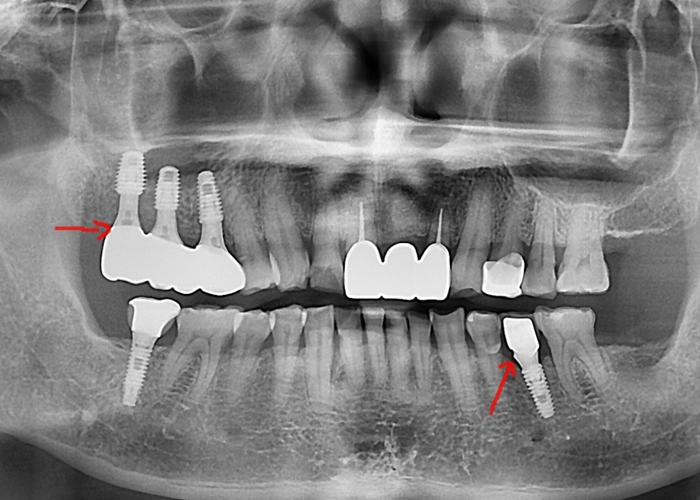

오른쪽 위 어금니를 발치한 환자분이

내원하셨습니다.

오래된 브릿지 보철물이 탈이 나면서

뿌리까지 손상된 상황이었고,

이미 어금니임플란트 경험도

있으셨습니다.

문제는

발치 직후라 잇몸과 뼈가

충분히 회복되지 않았다는 점이었습니다.

치아 흔적이 그대로 보이고,

뼈와 잇몸 모두 부족한 상태였죠.

발치 직후

어려운 조건이었지만,

울산 어금니임플란트를 단단하게 심어

안정적인 고정을 확보했습니다.